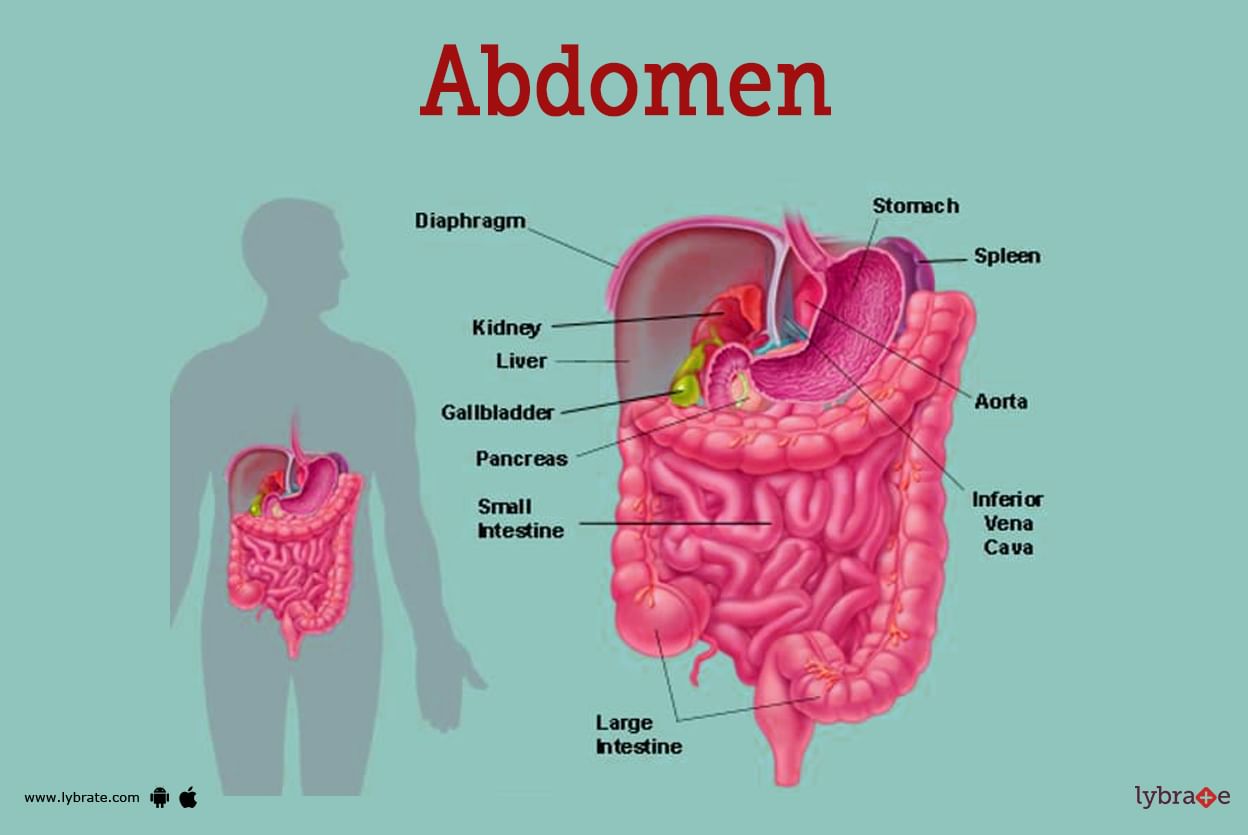

Abdomen Human Anatomy Image Definition Function Diseases And More

https://assets.lybrate.com/f_auto,c_limit,w_3840,q_auto/imgs/tic/enadp/image-of-the-abdomen.jpg

Abdomen Human Anatomy Image Definition Function Diseases And More